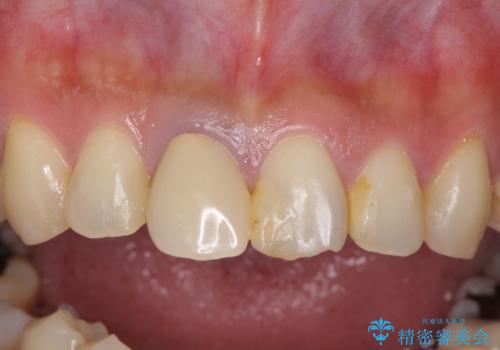

部分矯正を行った後にインプラント埋入と手前の歯の根管治療を行い、その後補綴治療を行うこととしました。

治療途中より、上の歯や反対側の銀歯、上顎前歯の色合いや下顎前歯のデコボコが気になってきたため、全てを治療することとしました。